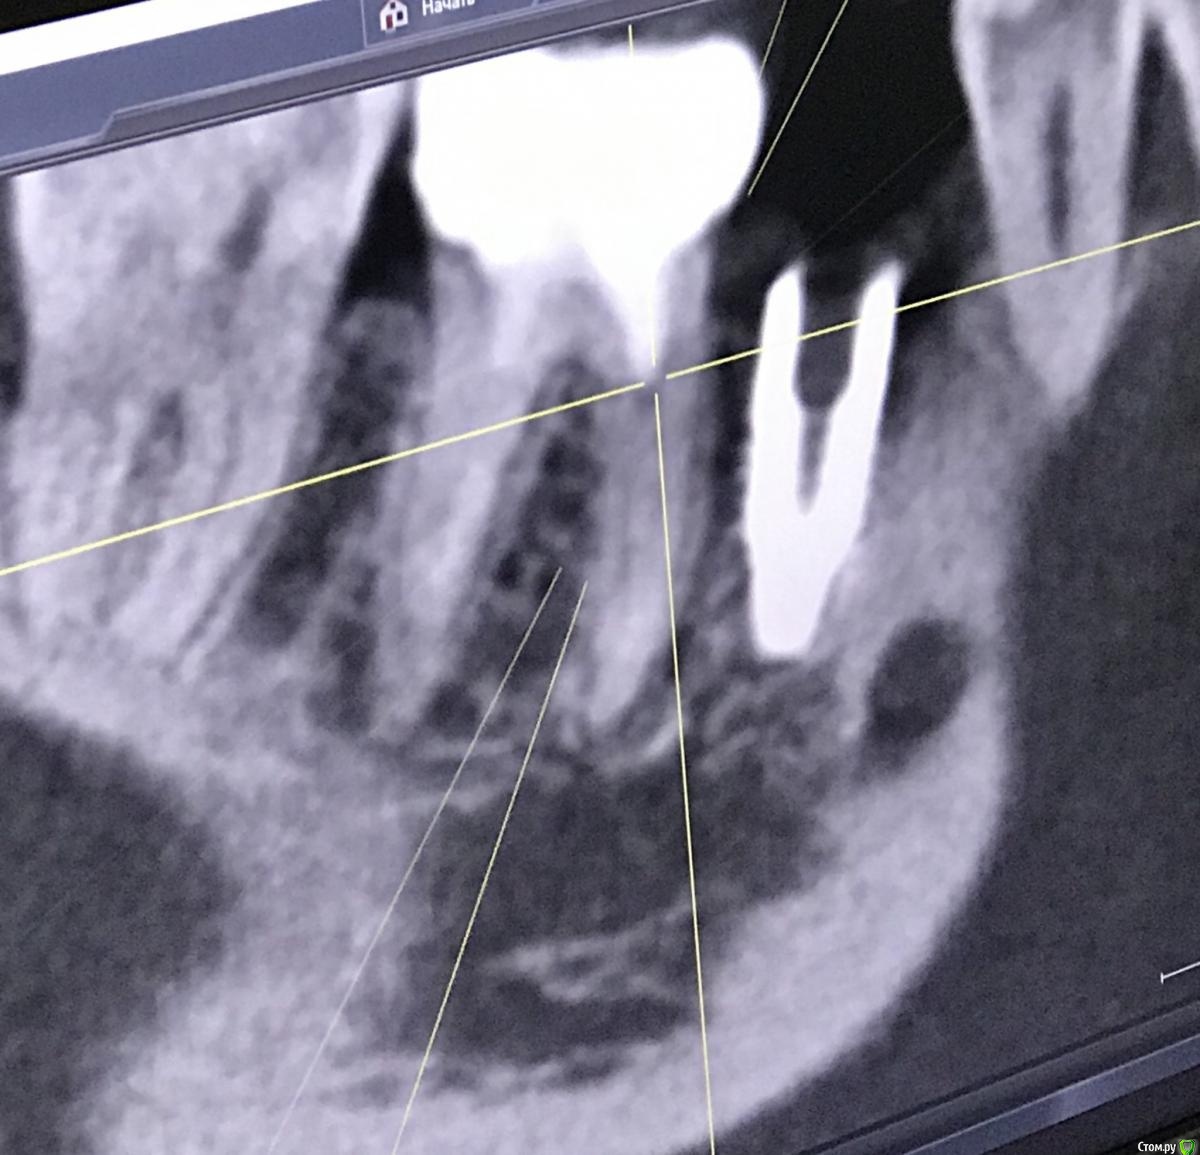

111 Опубликовано 25 декабря, 2020 Поделиться Опубликовано 25 декабря, 2020 Здравствуйте, уважаемые доктора,Посмотрите, пожалуйста, снимки и дайте Ваше видение ситуации.Субъективно - иногда с пульсацией побаливает область между 45 и 46. Но не часто совсем. Сам по себе 46 никаких ощущений не вызывает, был пролечен под микроскопом. Ортопедию не делали из-за наблюдения за 45. Ссылка на комментарий

111 Опубликовано 26 декабря, 2020 Автор Поделиться Опубликовано 26 декабря, 2020 (изменено) Iroil, спасибо большое за ответ.46 был кариес но не болел, периодонтита не было, никаких воспалений на верхушках не было. То есть 46 просто пролечили - обработали каналы, заложили кальций, и тд. Делалось под микроскопом, доктор очень хороший. По поводу 45 - изначально кости было достаточно по высоте, по объему пришлось подсыпать gen-oss 0,5 в момент имплантации, плюс сст с бугра. Вообще всё было хорошо, особо сильно не болело, без отёка зажило. В момент снятия швов - обнаружилась убыль кости в области 46, слегка оголился корень ближайший к 45, но мы как-то это не обсуждали с доктором. Установили Фдм, все ок.И вот пришло время ортопедии - это было летом 2019 - ортопед не захотел работать с имплантом, у которого на снимке оголена шейка. Десны достаточно при этом. Имплант не запротезирован.Спустя пару дней на визите у хирурга - я прошу выкрутить 45, мне отказывают, принято решение либо оставить как есть, либо подсыпать кости немного.Сейчас, декабрь 2020, я хожу с фдм и уже точно понимаю, что надо переустановить 45, но хирург предлагает 2 варианта:- оставить как есть и делать ортопедию (т.к. десна хорошая);- удалить 45 и 46 для создания удобного рабочего поля и имплантация 45, 46.Вот я пытаюсь понять, нельзя ли просто 45 выкрутить? Аккуратно удалить 45 не получится? (Очень не хочется расставаться с 46, сам по себе он не болит при накусывании и постукивании). Изменено 26 декабря, 2020 пользователем 111 Ссылка на комментарий

Irouil Опубликовано 26 декабря, 2020 Поделиться Опубликовано 26 декабря, 2020 Не вижу явных причин удалять зуб. Удалять зуб ради удаления имплантата - такого ещё не слышал 1 Ссылка на комментарий